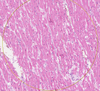

Brown Myocardial Atrophy Flashcards

Brown Myocardial Atrophy

Lipofuscin

Atrophic Cardiac Myocytes